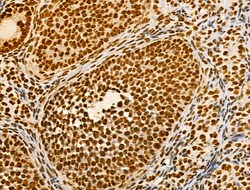

| Immunohistochemistry (Paraffin), Western Blot, Immunocytochemistry | |